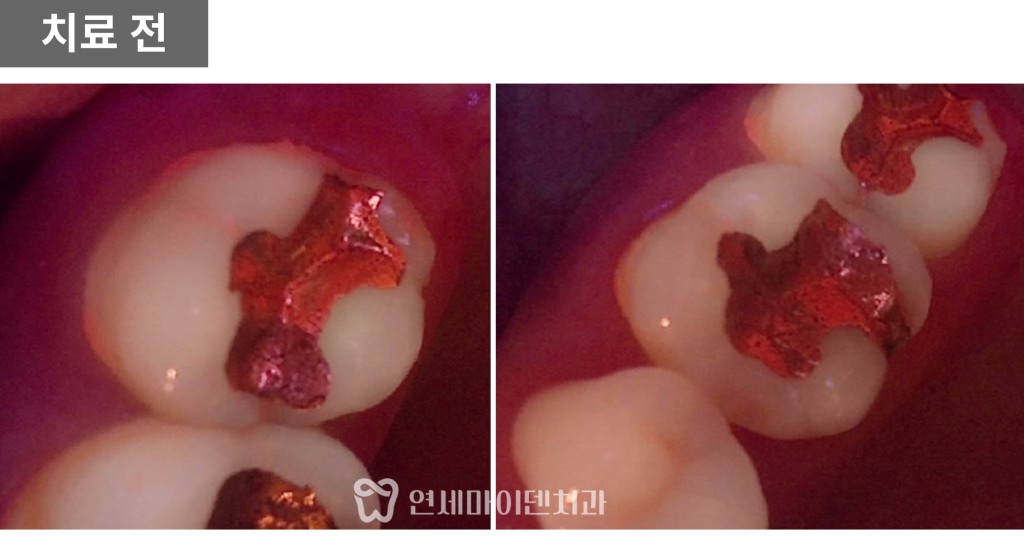

실제로 보철물을 제거하고

내부를 확인해보니

통증의 원인은 크랙이 맞았습니다.

크랙 치아 치료의 원칙

크랙 치아의 치료 원칙은 명확합니다.

가능하다면 신경치료를 하지 않고

크라운으로 보호하는 것이 가장 좋습니다.